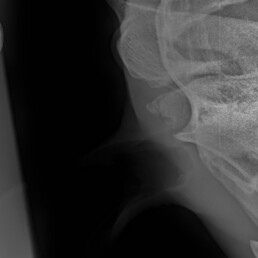

Weiterführende Untersuchungen: Röntgen

- makroskopische Umfangsvermehrung am linken Kiefergelenk

- röntgenologische Untersuchung beider Kiefergelenke zum Seitenvergleich

- beidseitige Befunde

Diagnose: beidseitige Kiefergelenksarthrose